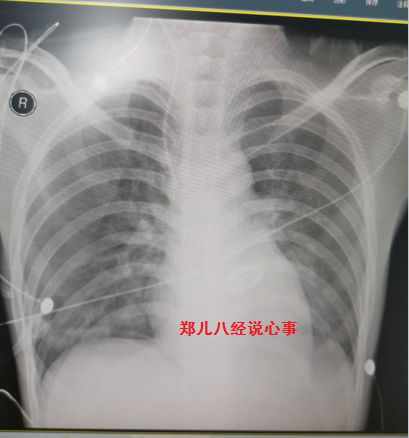

图3 术后胸片与图1胸片时间仅差4天,术后肺水肿迅速消失,胸片上典型的双侧肺门蝶形影消失

明确心源性肺水肿、感染性心内膜炎、二尖瓣赘生物并重度关闭不全,加强利尿治疗同时启动手术程序。术中及术后病理证实为慢性心内膜炎。术后心肺功能好转,复查胸片双侧肺门蝶形影消失(图3)。